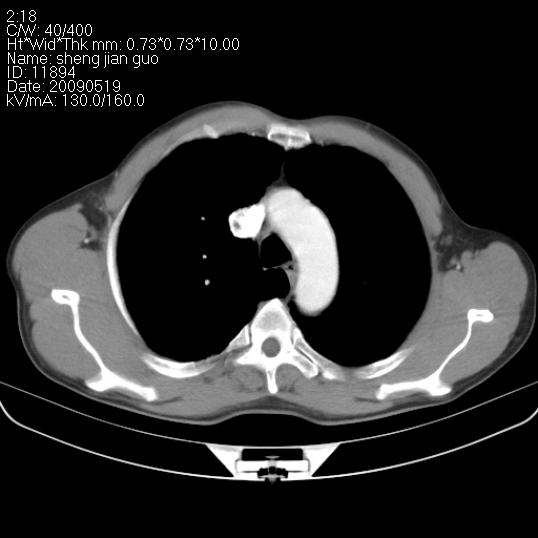

以下是引用zjzjr在2009-5-19 17:25:00的发言:[br]支持楼主考虑,另左肺下叶阻塞性炎症。

以下是引用zhao_bin2008在2009-5-19 17:48:00的发言:[br]支持左肺下叶周围型肺癌并阻塞性肺炎。

以下是引用zsl6918在2009-5-20 7:10:00的发言:[br]左侧中心型肺癌!